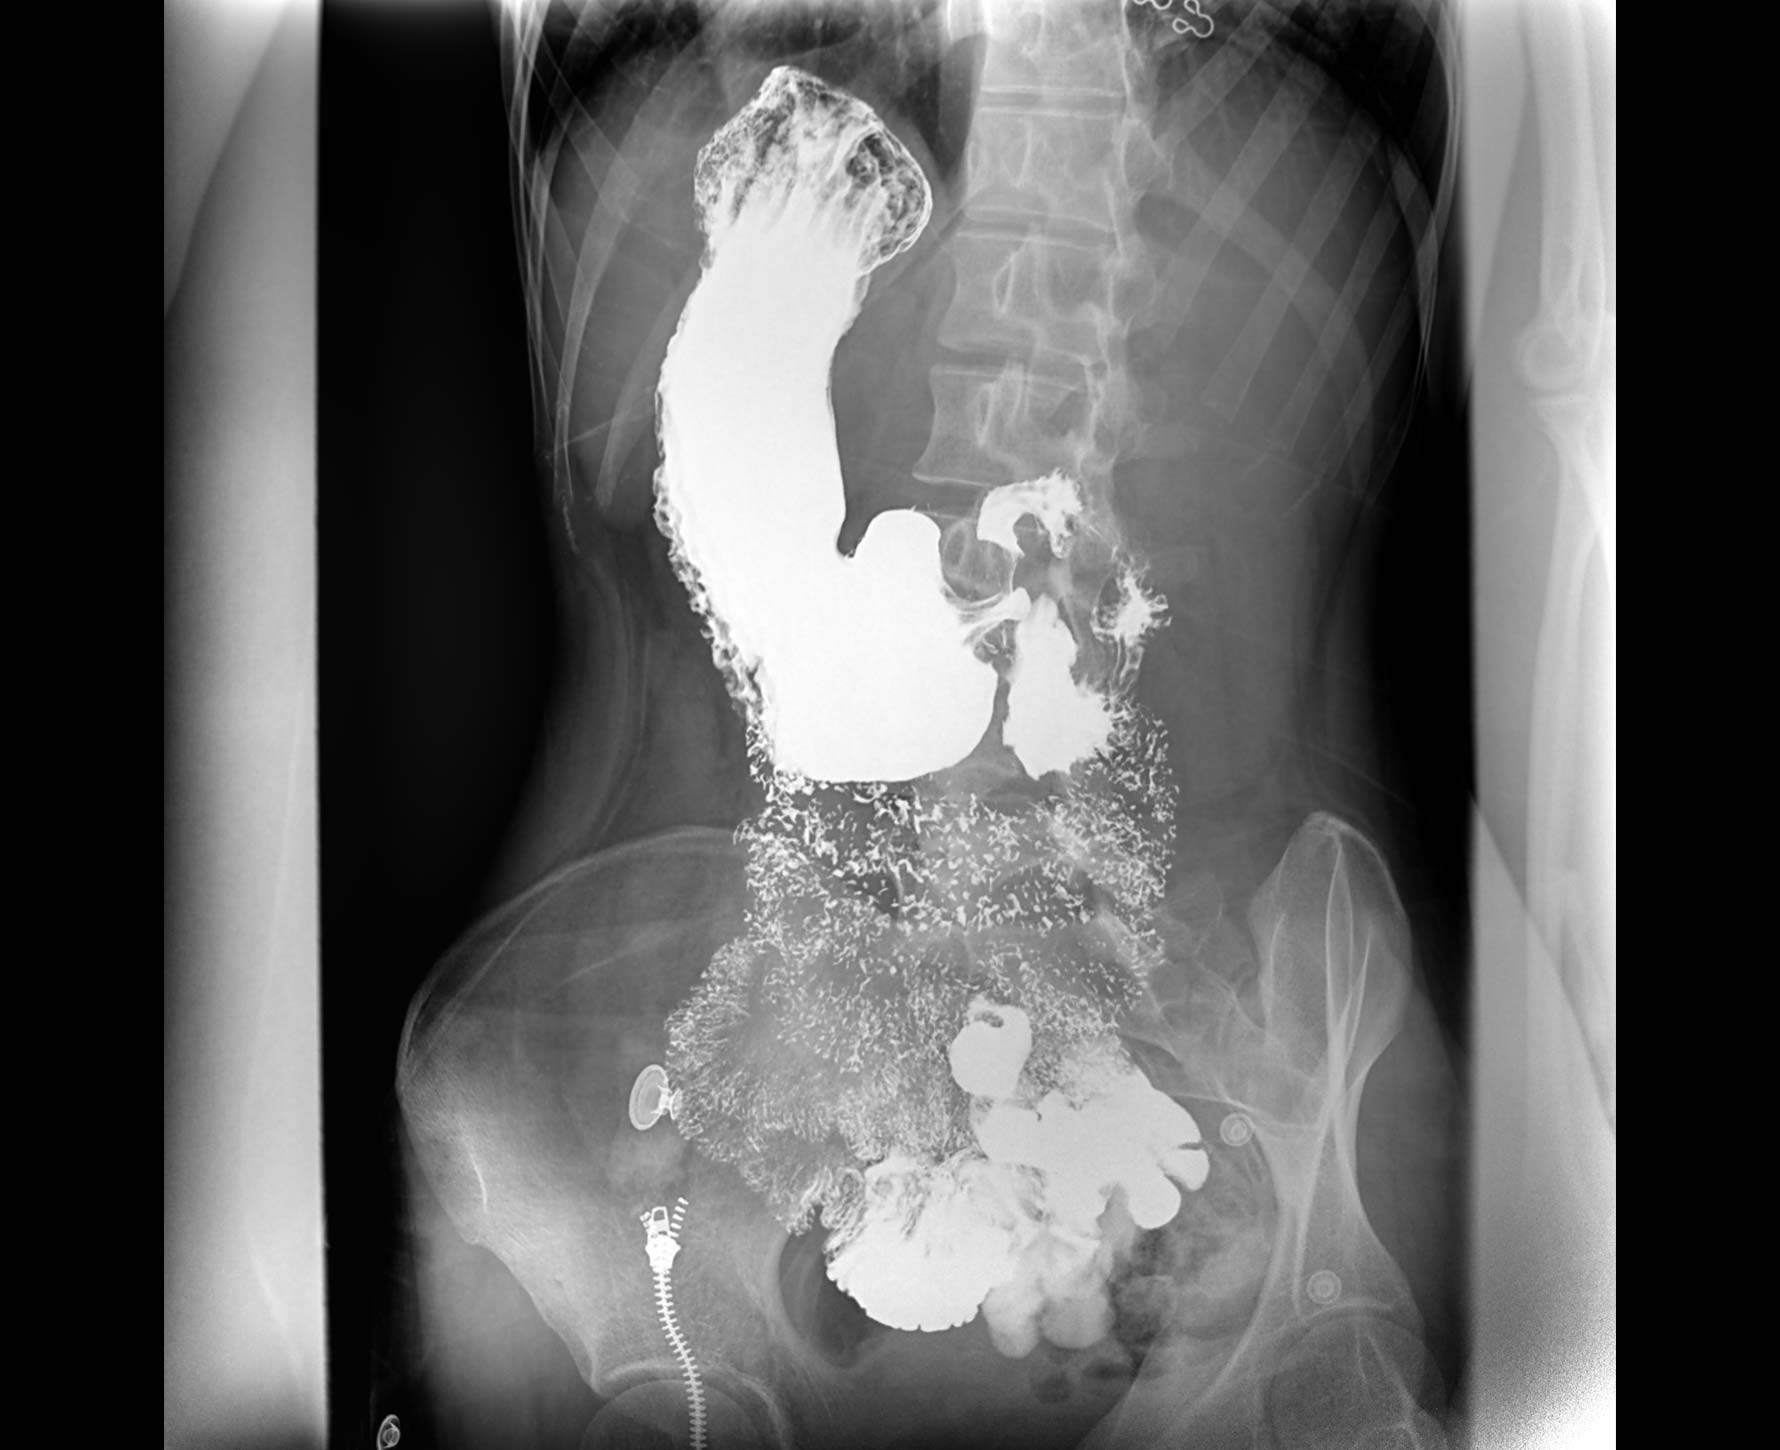

• 造影

适用于各种普通

及特殊胃肠造影检查

• 特有视频保存与回放功能

对胃肠造影检查影像实时保存,多次回放以便确定病灶部位,患者确诊好帮手,减少漏诊。